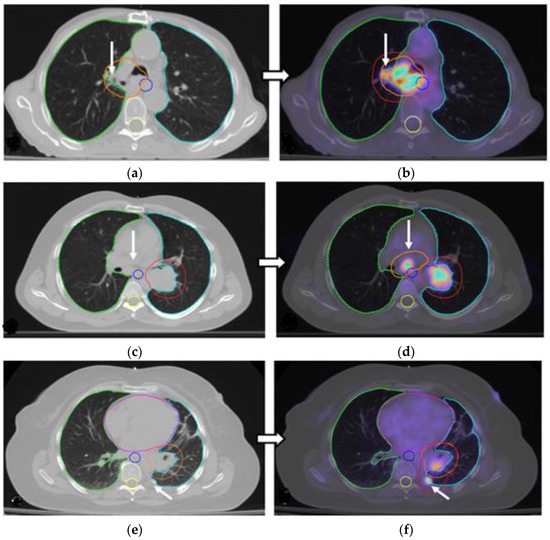

3.2. Changes in the Primary Tumor and Nodal Coverage